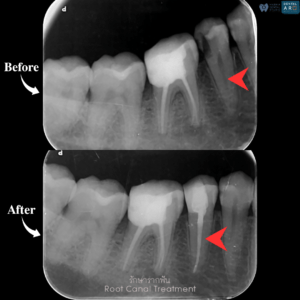

รักษารากฟัน

คือ การรักษาฟันที่เกิดการอักเสบและติดเชื้อภายในโพรงประสาทฟัน และเนื้อเยื่อรอบปลายรากฟัน อันมีสาเหตุมาการอักเสบและติดเชื้อภายในรากฟัน โดยทันตแพทย์จะทำการทำความสะอาดและใส่ยาในคลองรากฟัน และทำการอุดรากฟันเป็นขั้นตอนสุดท้าย การรักษารากฟันจะช่วยเก็บรักษาฟันให้สามารถคงอยู่ในช่องปากต่อได้ โดยไม่ต้องถอนฟันและไม่ต้องใส่ฟันทดแทน